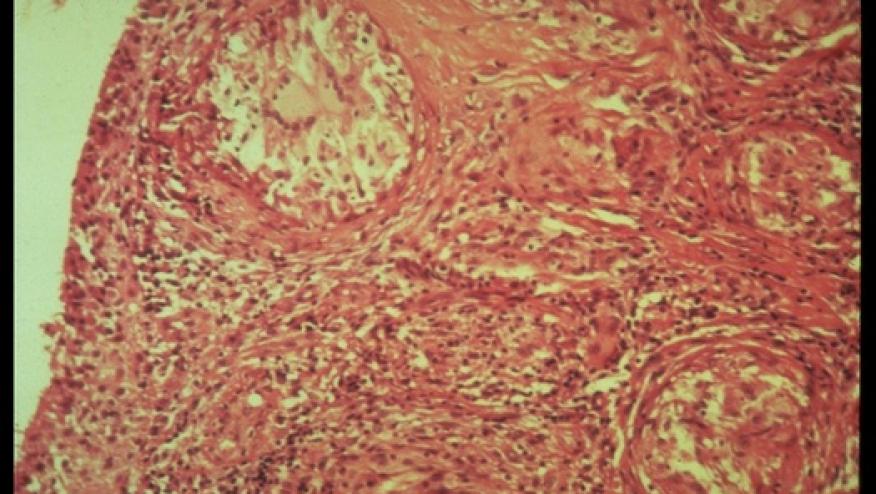

There is biologic rationale for this approach as JAK- STAT signaling plays a role in the pathogenesis of sarcoidosis. The authors performed RNA sequencing on biopsied lesions before and during treatment, showing evidence of the Jak-STAT pathway is going from active to inactive. This, coupled with clinical and histologic remission of her skin disease suggests the potential benefit of tofacitinib.